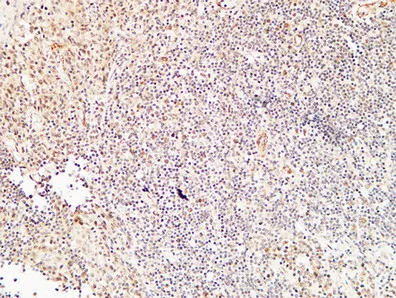

Cleaved-Caspase-9 p35 (D315) Rabbit Polyclonal Antibody

Cat: APRab08971

Cleaved-Caspase-8 (D384) Rabbit Polyclonal Antibody

Cat: APRab08968